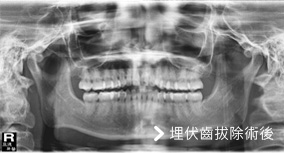

此為埋伏齒手術前後對照照片,照片的左邊其實是病人的右邊。從照片上可以看到左右下牙床智齒成水平狀態,屬於難度高的手術,需開刀拔除。

但轉診的大醫院往往安排數星期才能拔,無法即時解決問題。亞德擁有一流的設備及完善儀器,安排後即可拔牙。免除病人舟車勞頓之苦,且可在術後得到良好的照護。